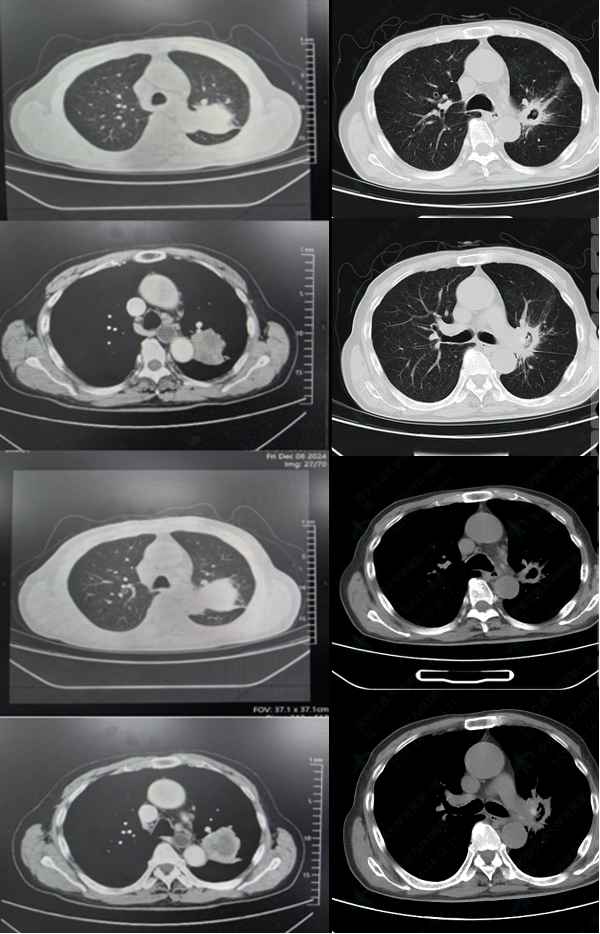

• 2024-12-6胸部CT:左肺肿物

图1 2024-12-6胸部CT

2025-1-17 首次用药后,胸部CT结果如下,提示病灶明显缩小;

图7 2024-12-6(左)对比2025-01-17(右)胸部CT

2025-04-26 用药5周期后,胸部CT结果如下所示,疗效评估为PR

图8 2024-12-6(左)对比2025-04-26(右)胸部CT